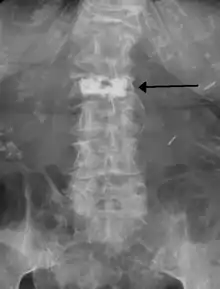

وعادة ما يتم إجراء رأبُ الفقرة على يد جراح العمود الفقري أو أخصائي التدخل الإشعاعي وهو إجراء الحد الأدنى للغزو، وغالبا ما يعود المرضى إلى المنزل في نفس يوم العملية أو اليوم التالي ويتم إعطاء المرضى التخدير الموضعي والتخدير الخفيف في العملية بالرغم من أنه يمكن القيام بها باستخدام مخدر موضعي فقط للمرضى الذين يعانون من مشاكل صحية والمرضى الذين لا يستطيعون تحمل المهدئات بشكل جيد. خلال العملية، يتم حقن ملاط العظام مع خزعة الإبرة في الفقرة المنهارة أو المكسورة، يتم وضع الإبرة مع جهاز الأشعة السينية التوجيهي، ويتصلب الملاط (puma وهوالأكثر شيوعا، بالرغم من وجود الكثير من الملطات الحديثة التي تستخدم جيدا) بسرعة ليشكل الهيكل الداعم داخل الفقرة الذي يوفرالإستقرار والقوة، وتكون الإبرة فجوة في جلد المريض والتي يمكن تغطيتها بسهوله بعد القيام بهذا الاجراء.

بعض المخاطر المرتبطة برأب الفقرة هي من تسرب الملاط الاكريليك إلى خارج جسم الفقرة، وعلى الرغم من أن المضاعفات الشديدة نادره جدا إلا أنه يمكن أن ينجم عنها العدوى والنزيف والخدر والوخز والصداع والشلل بسبب سوء وضع الإبرة أو الملاط في موضعه، وتقل هذه الأخطار باستخدام الأشعة السنية أو الصور الإشعاعية الأخرى لضمان الوضع المناسب للملاط، ويظهر خطر الأحداث الخطيرة الضارة ليبدو أكبر بنحو 2% لأولئك الأشخاص الذين لديهم كسور بسبب السرطان. لا يظهر خطر الإصابة بكسور جديدة بعد هذه الإجراءات ليتم تغييرها، ومع ذلك فإن الأدلة محدودة ولم يتم استبعاد زيادة الخطر خلال عام 2012 وقد ذكر بأن الانسداد الرئوي بسبب الملاط يحدث في ما يقارب 2-20% من الإجراءات ويمكن أن يحدث بدون أعراض وعادة أن لم يكن هناك أعراض فلا يوجد قضية طويلة المدى. وتظهر الأعراض تقريبا في 1 من 2000 إجراء، وتشمل الآثار السلبية الأخرى إصابة الحبل الشوكي في 0.6 لكل 1000.